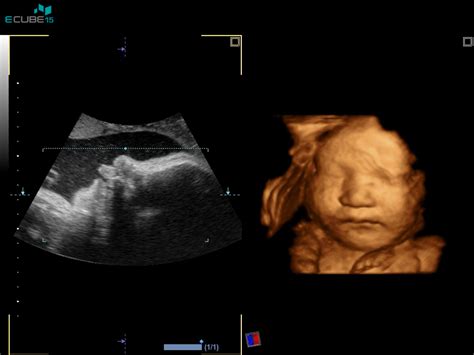

Pregled nuhalne svetline poteka z ultrazvokom, običajno preko trebuha nosečnice (transabdominalni ultrazvok). Le v redkih primerih, na primer ob neugodnem položaju ploda ali večji telesni masi nosečnice, je potreben vaginalni ultrazvok (transvaginalni ultrazvok). Sam pregled običajno traja med 10 in 15 minutami, odvisno od položaja ploda.

Pred pregledom ni posebnih priprav. Nosečnica ne potrebuje biti na tešče. Priporočamo udobna oblačila s preprostim dostopom do trebuha. Pomembno je, da se nosečnica pred pregledom popolnoma izprazni mehur, kar omogoča boljšo vidljivost. Med samim pregledom ginekolog izmeri plodovo srčno frekvenco, velikost od vrha glavice do trtice, premer glavice, preveri prisotnost nosne kosti, oceni obliko glavice in možganskih struktur. Pregledajo se tudi srce, želodček, mehur ter preveri se, ali je trebušna stena v celoti prekrita s kožo. Pregledajo se dolge kosti na zgornjih in spodnjih udih ter hrbtenica.

Partner je dobrodošel, da spremlja nosečnico med pregledom. Med preiskavo ginekolog razloži, kaj je videti na ultrazvočni sliki in kako se interpretirajo rezultati. Po želji se lahko pogovorite tudi o možnosti zgodnjega ugibanja o spolu ploda, čeprav ta v tem stadiju še ni stoodstotno zanesljiva.